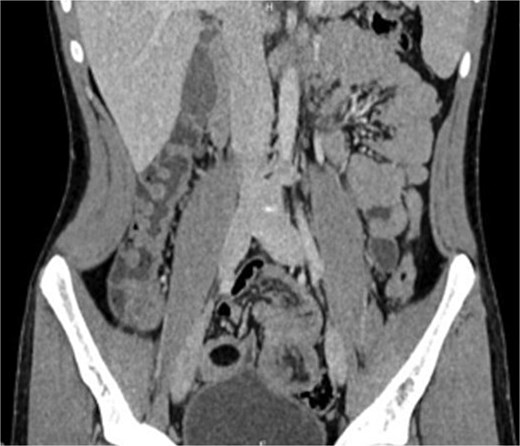

Emergency laparotomy revealed a jejuno-jejunal intussusception 60 cm distal to the ligament of Treitz (Fig. 3). Manual reduction exposed a compound ileo-ileal intussusception without vascular compromise (Fig. 4). The intramural lipoma was subsequently identified (Fig. 5). Resection and end-to-end anastomosis of the involved ileal segment, with a 5-cm safety margin on each side, were performed.

Preoperative view of manual reduction exposed a compound ileo-ileal intussusception without vascular compromise.

Histopathological examination confirmed a submucosal intestinal lipoma with no dysplasia or malignancy. The postoperative course was uneventful, and the patient was discharged after 5 days.